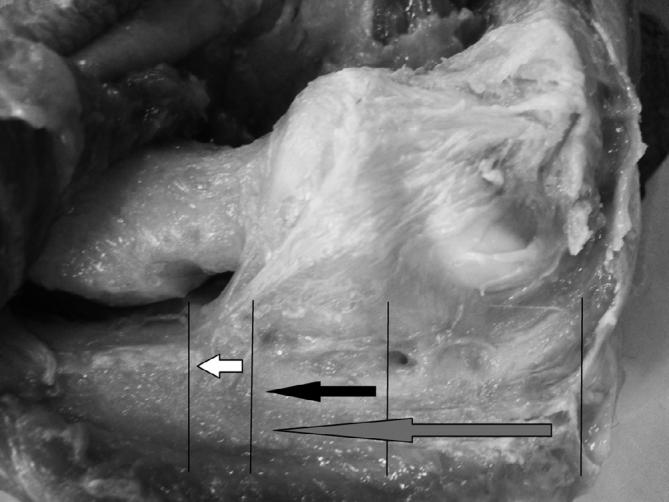

Thirteen elbows of eight fresh cadavers were dissected for the study of the LUCL. The distances between the proximal and distal insertion of the LUCL (footprint), between the radial head and the footprint and between the olecranon tip and the footprint were measure with a digital pachimeter.

The average distance from the radial head to the proximal and distal ulnar insertion of the LUCL was 13.6 and 22.99 mm, respectively. The average distance between the olecranon tip and the proximal and distal ulnar insertion of the LUCL was 38.25 and 47.6 respectively. The mean length of the LUCL footprint was 9.35 mm.

The LUCL insertion has a wide footprint with average 9.3 mm (7.5-11 mm). Ulnar insertion half point be located at 18.2 mm of the radial head and at 42.9 mm of olecranon tip.

对8具新鲜尸体的13个肘关节进行解剖,以研究LUCL。用数字厚度仪测量LUCL近端和远端附着点(足迹)之间、桡骨头与足迹之间以及尺骨鹰嘴尖与足迹之间的距离。

从桡骨头到LUCL尺骨近端和远端附着点 的平均距离分别为13.6毫米和22.99毫米。尺骨鹰嘴尖与LUCL尺骨近端和远端附着点之间的平均距离分别为38.25毫米和47.6毫米。LUCL足迹的平均长度为9.35毫米。

LUCL附着点有一个较宽 的足迹,平均为9.3毫米(7.5 - 11毫米)。尺骨附着点中点位于距桡骨头18.2毫米处和距尺骨鹰嘴尖42.9毫米处。